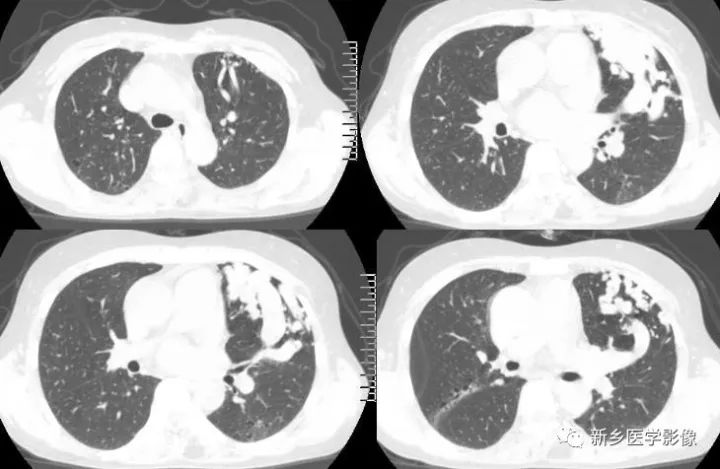

影像学表现

X线胸片:表现为肺外带类圆形结节影,部分病灶边缘可见指向肺门的增粗血管影。

根据相关文献报道:

国内将X线表现分为3类

1.结节型 直径<3cm,边缘清晰,密度均匀 2.团块型 直径3-8cm,可有分叶,密度均匀或不均匀 3.弥漫型 肺野散在多个病灶,呈逗点状影,诊断相对较困难 肺动脉造影是诊断金标准,但为有创性。 CT平扫:肺部单发、多发结节或囊袋状影 CTA:①血管蒂征,扩张的血管囊边缘有供血动脉及引流静脉 ②动脉瘤、供血动脉与胸部供血大血管强化一致,引流肺静脉及左心房提前显影。 国外CT表现分型: 1.可分辨解剖结构型 引入动脉及引流静脉 2.结节型 密度均匀结节状影,CT增强病灶直径增大1cm,并与大血管同步强化可确诊。 3.管状型 分隔或不分隔的弓状影 鉴别诊断 1.炎性假瘤:多有炎性病史,边缘呈“方形征”或“刀切征”,增强扫描呈均匀强化,但强化程度不及PAVM。 2.肺癌:边缘分叶、毛糙,周围有浸润,有阻塞改变,增强强化程度不及邻近大血管 3.结核球:边缘光滑或有长毛刺,其内密度较低,可见钙化灶,周围可见卫星灶。增强扫描不强化或边缘强化。 4.肺内富血供结节病灶:主要由支气管动脉供血,时间密度曲线应与左心室与主动脉强化时间一致,且肺内富血供实质结节病灶多为恶性病变,边缘不光整,可见毛刺、分叶 5.肺静脉曲张:为肺静脉局限性扩张,临床很少有症状。一般认为是肺静脉壁先天性缺陷或肺静脉高压造成。病灶靠近左心房,CT扫描两下肺内圆形、椭圆形或管状明显强化,强化程度与左心房一致,无PAVM特征性的供血动脉和引流静脉。